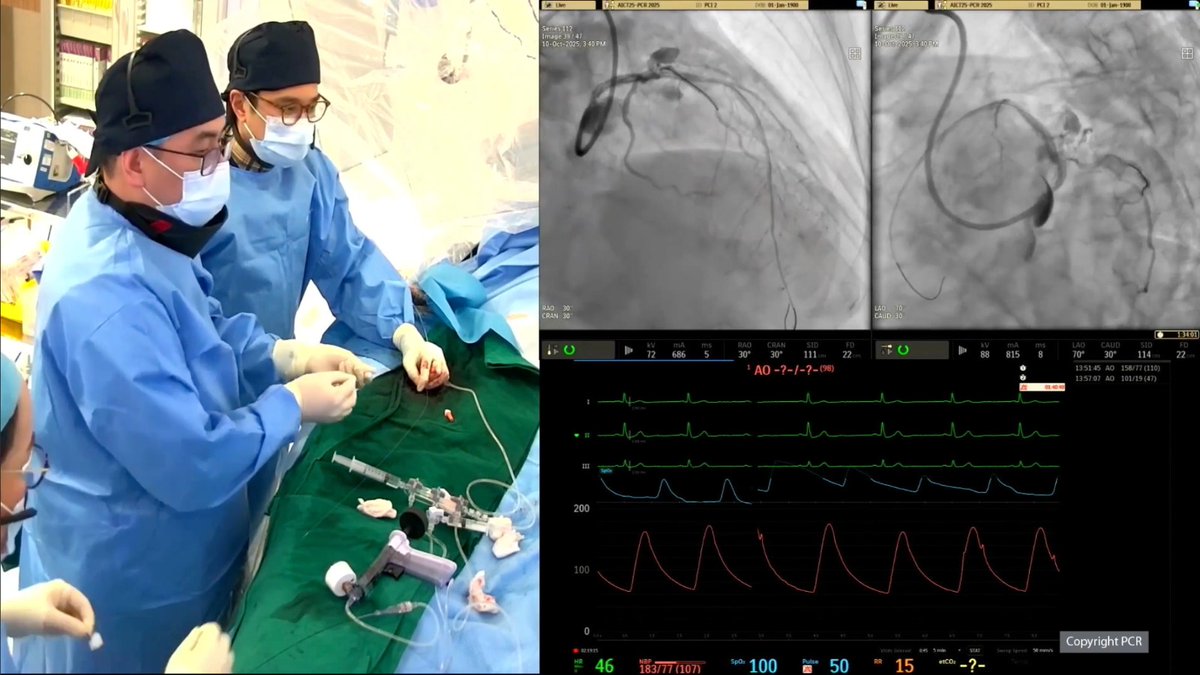

Pushing the frontiers of heart care ❤️ A proud moment for #NUHCS at #AVPlusCONNECT Modern PCI LIVE - Prof Tan Huay Cheem, Senior Advisor, & Dr Christopher Koo, Consultant, successfully performed a complex live heart procedure among 9 global collaborations & 80 live cases. 👏

AICT-AsiaPCR 2025, a major cardiology conference, gathered over 1,000 experts for 2 days of learning. #NUHCS presented 4 complex treatment procedures led by A/Prof Mark Chan, A/Prof Adrian Low, Adj A/Prof Loh Poay Huan, Asst Prof Ivandito Kuntjoro, Dr Gavin Ng & Dr Qian Qi.